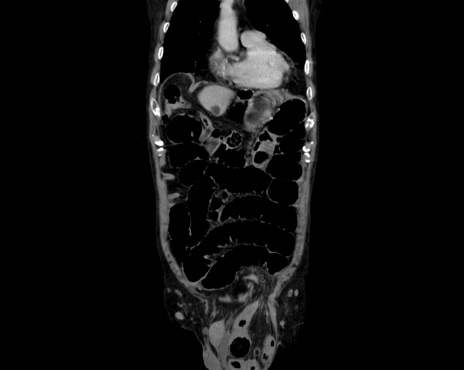

症例26(冠状断像)

【症例】80歳代男性

【主訴】嘔吐

【現病歴】昨晩2回嘔吐あり、今朝になっても嘔吐あり。来院。

【既往歴】胃潰瘍

【身体所見】意識清明、BT 37.6℃、BP 166/95mmHg、HR 100bpm、SpO2 97%、腹部:平坦・軟、腸蠕動音聴取良好、圧痛なし。

【データ】WBC 21900、CRP 1.4